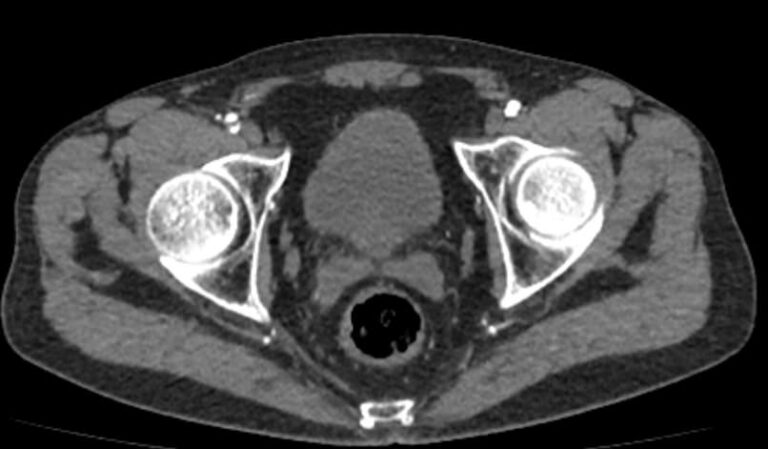

Назад КТ брюшного отдела аорты и сосудов (артерий) нижних конечностей

Основные показания для проведения КТ брюшного отдела аорты и артерий нижних конечностей могут включать:

• Аневризмы: оценка и диагностика аневризм брюшной аорты.

• Стенозы и окклюзии: выявление и оценка степени сужения или блокировки артерий.

• Тромбозы: обнаружение тромбов и оценка их размера и локализации.

• Атеросклероз: определение степени и распространенности атеросклеротических изменений.

• Подготовка к хирургическим вмешательствам: планирование сосудистых операций и вмешательств.

• Оценка послеоперационного состояния: контроль за состоянием сосудов после хирургических вмешательств.

• Контрастное усиление: контрастное вещество вводится внутривенно. Это помогает улучшить видимость сосудов на изображениях.

Преимущества КТ брюшного отдела аорты и артерий нижних конечностей включают:

• Высокая точность и детализация изображений.

• Быстрота выполнения исследования.

• Возможность трехмерной реконструкции сосудов.

В целом, КТ брюшного отдела аорты и артерий нижних конечностей является эффективным методом диагностики сосудистых заболеваний и играет важную роль в планировании лечения и оценки его результатов.